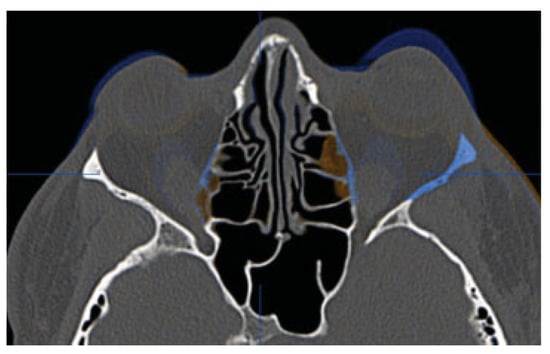

Three months after the decompression, the patient had a postoperative helical CT study. The postoperative imaging demonstrated the bony removal and decompression of the orbital soft tissues (Figure 5). Virtual stereolithographic models were generated from the DICOM data and used for direct comparison of the pre- and postoperative orbits (Figure 6).

In the cases discussed herein, we routinely perform Hertel exophthalmometry as it is reproducible and easy to perform. After lateral rim removal, we clinically measure A-P globe position using the Naugle exophthalmometer; however, we do not have measurements with the Naugle preoperatively in these two cases. Rather, the reduction in proptosis in these two patients was easily verified on their pre- and postoperative CT scan fusion (Figure 5 and Figure 10). Objective outcome assessment utilizing the position of the anterior cornea to the orbital superior (Os) and orbitale inferior (Oi) is ongoing and will be the goal of future works.

Figure 5. Fusion of preoperative (blue) and postoperative (orange) CT scans for patient 1. Uncolored portions are identical on the two scans.